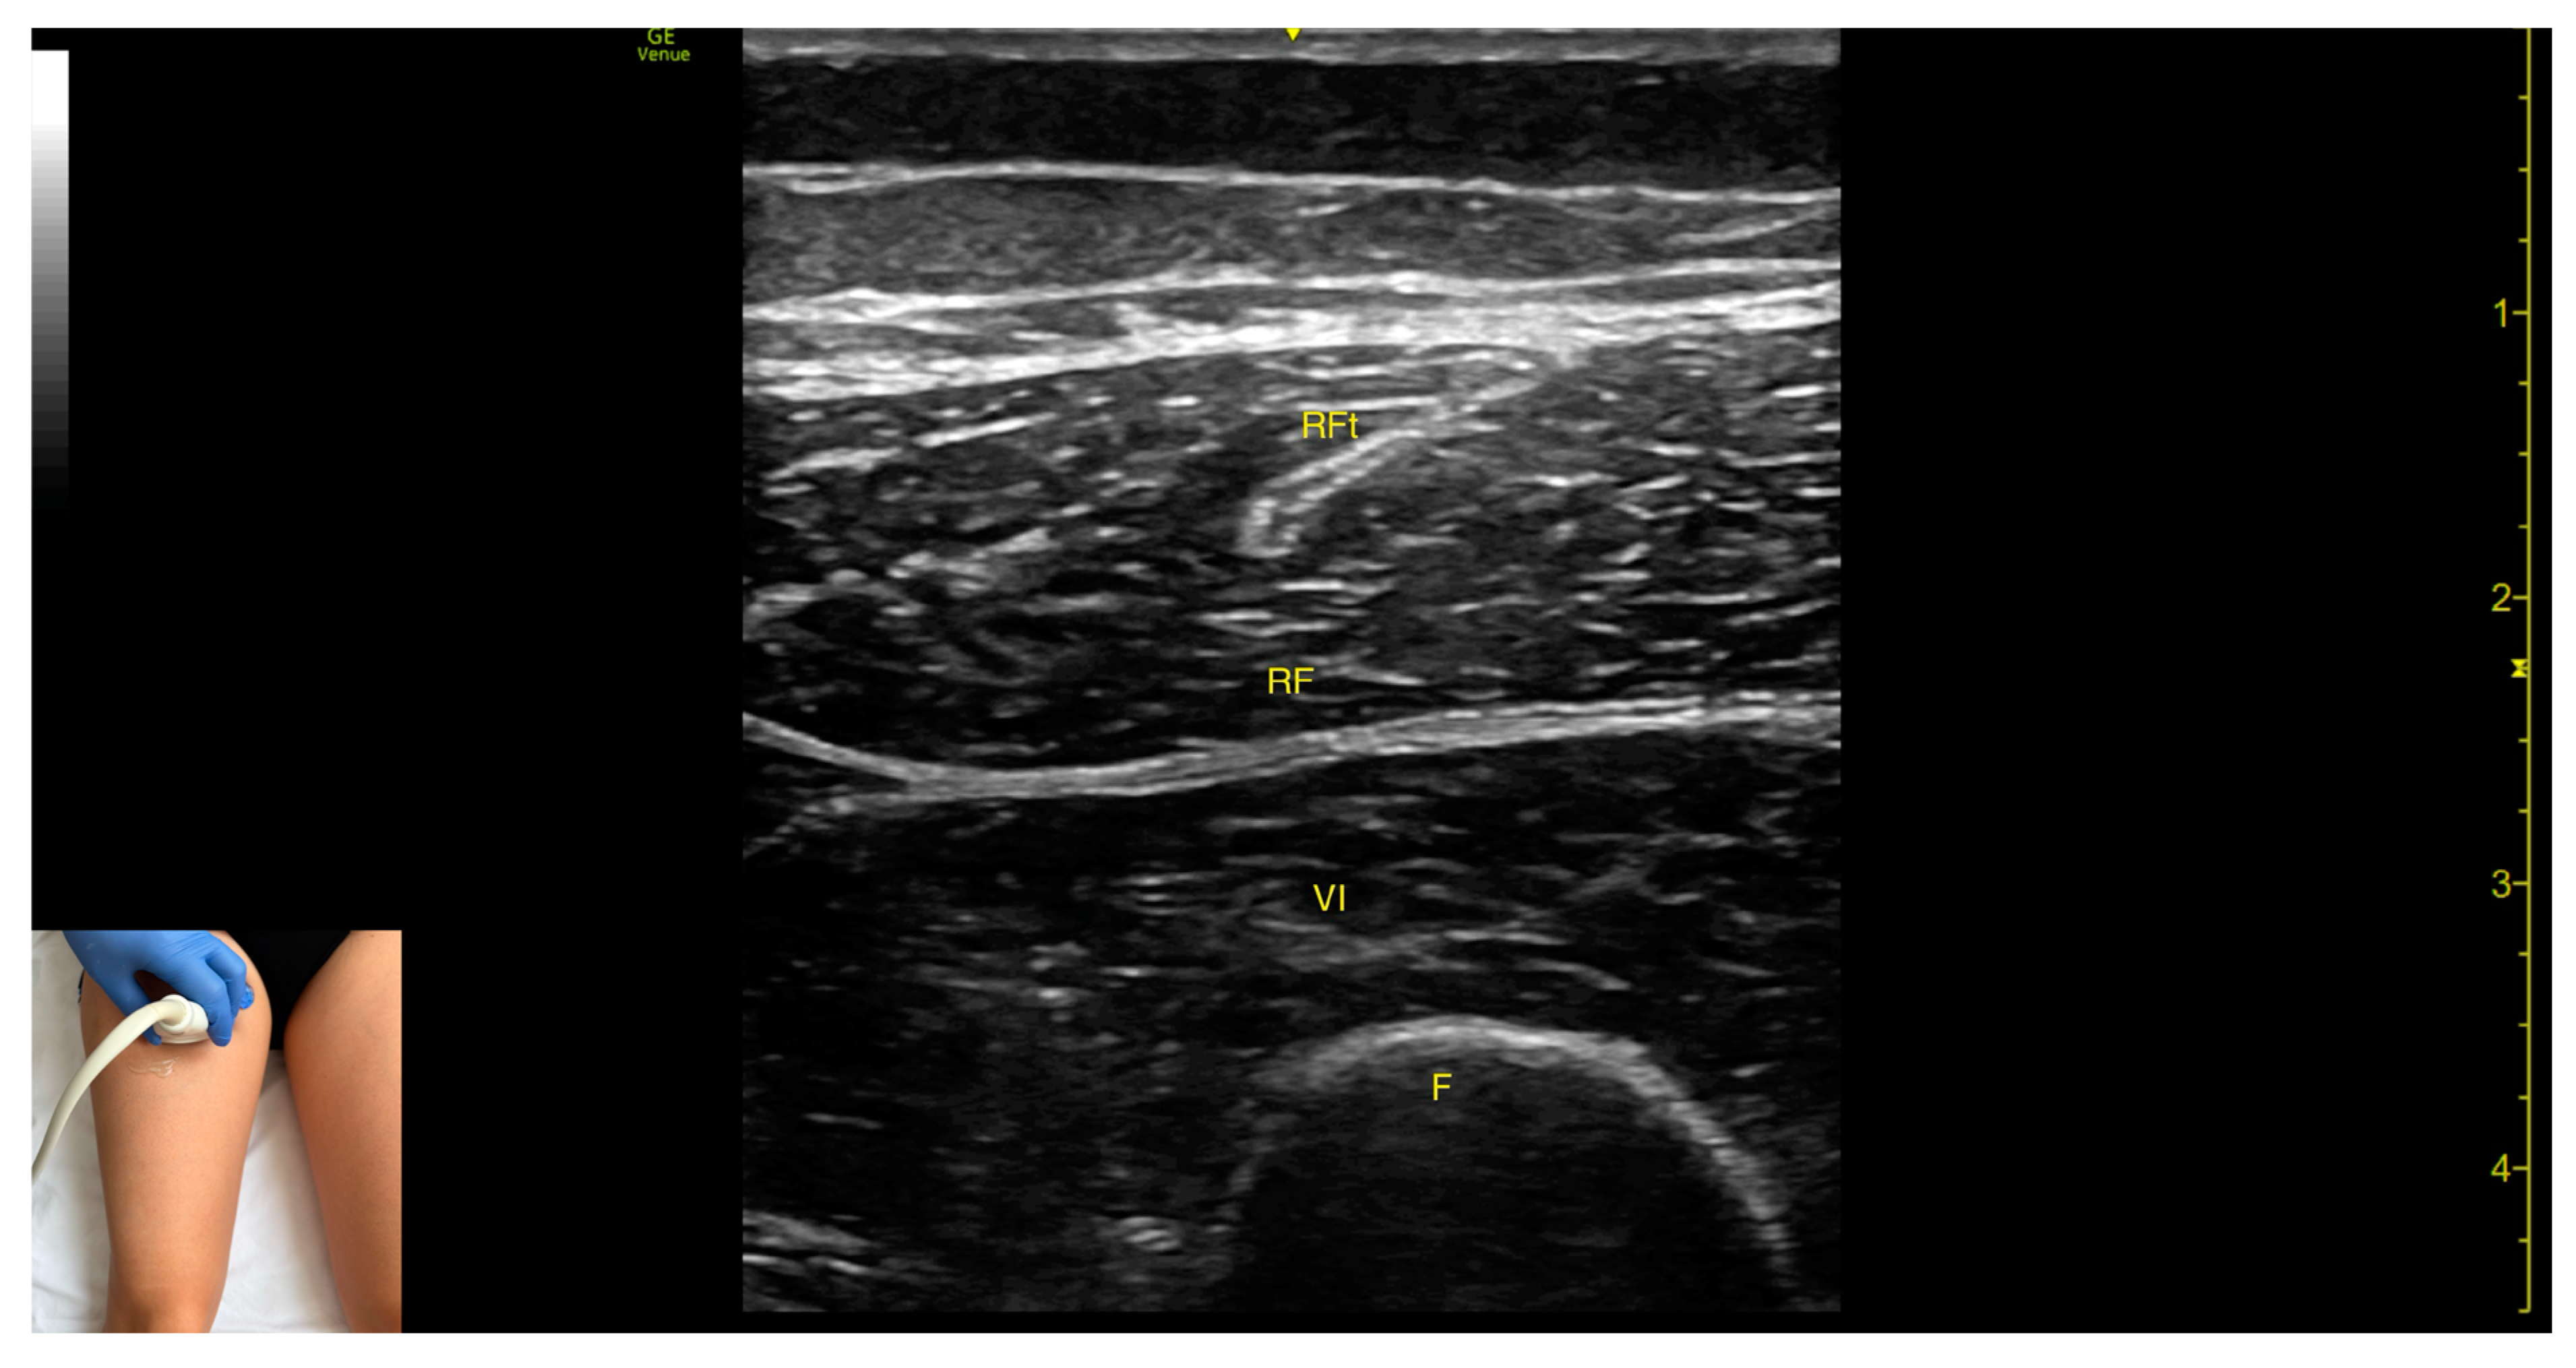

3.4. Rectus Femoris (RF)

3.4.2. Ultrasound Identification

3.4.3. Key Ultrasound Landmarks

- Muscle morphology: The RF is a bipennate muscle, characterized by a central septum, with muscle fibers attached on both sides and continuing into a central tendon. These two fiber regions should be individually targeted during injection

- Muscle position: It is the most superficial muscle mass at this level. Lateral to the rectus femoris lies the vastus lateralis, and medial to it, the vastus medialis.

- External fascia: A pronounced fascia separates the rectus femoris from the subcutaneous plane and adjacent muscles: vastus intermedius, vastus lateralis, and vastus medialis.

- Dynamic evaluation: During dynamic evaluation, scanning distally toward the knee joint, the muscle bulk of the RF decreases, but its central tendon remains visible until the distal third of the thigh (Video S1). Muscle contraction is visible during hip flexion and knee extension maneuvers.

3.4.4. Clinical Implications and Injection Strategy

| Rectus Femoris | Proximal third of anterior thigh; midline | Vastus intermedius (deep) | Transverse scan on anterior thigh | Avoid central tendon |